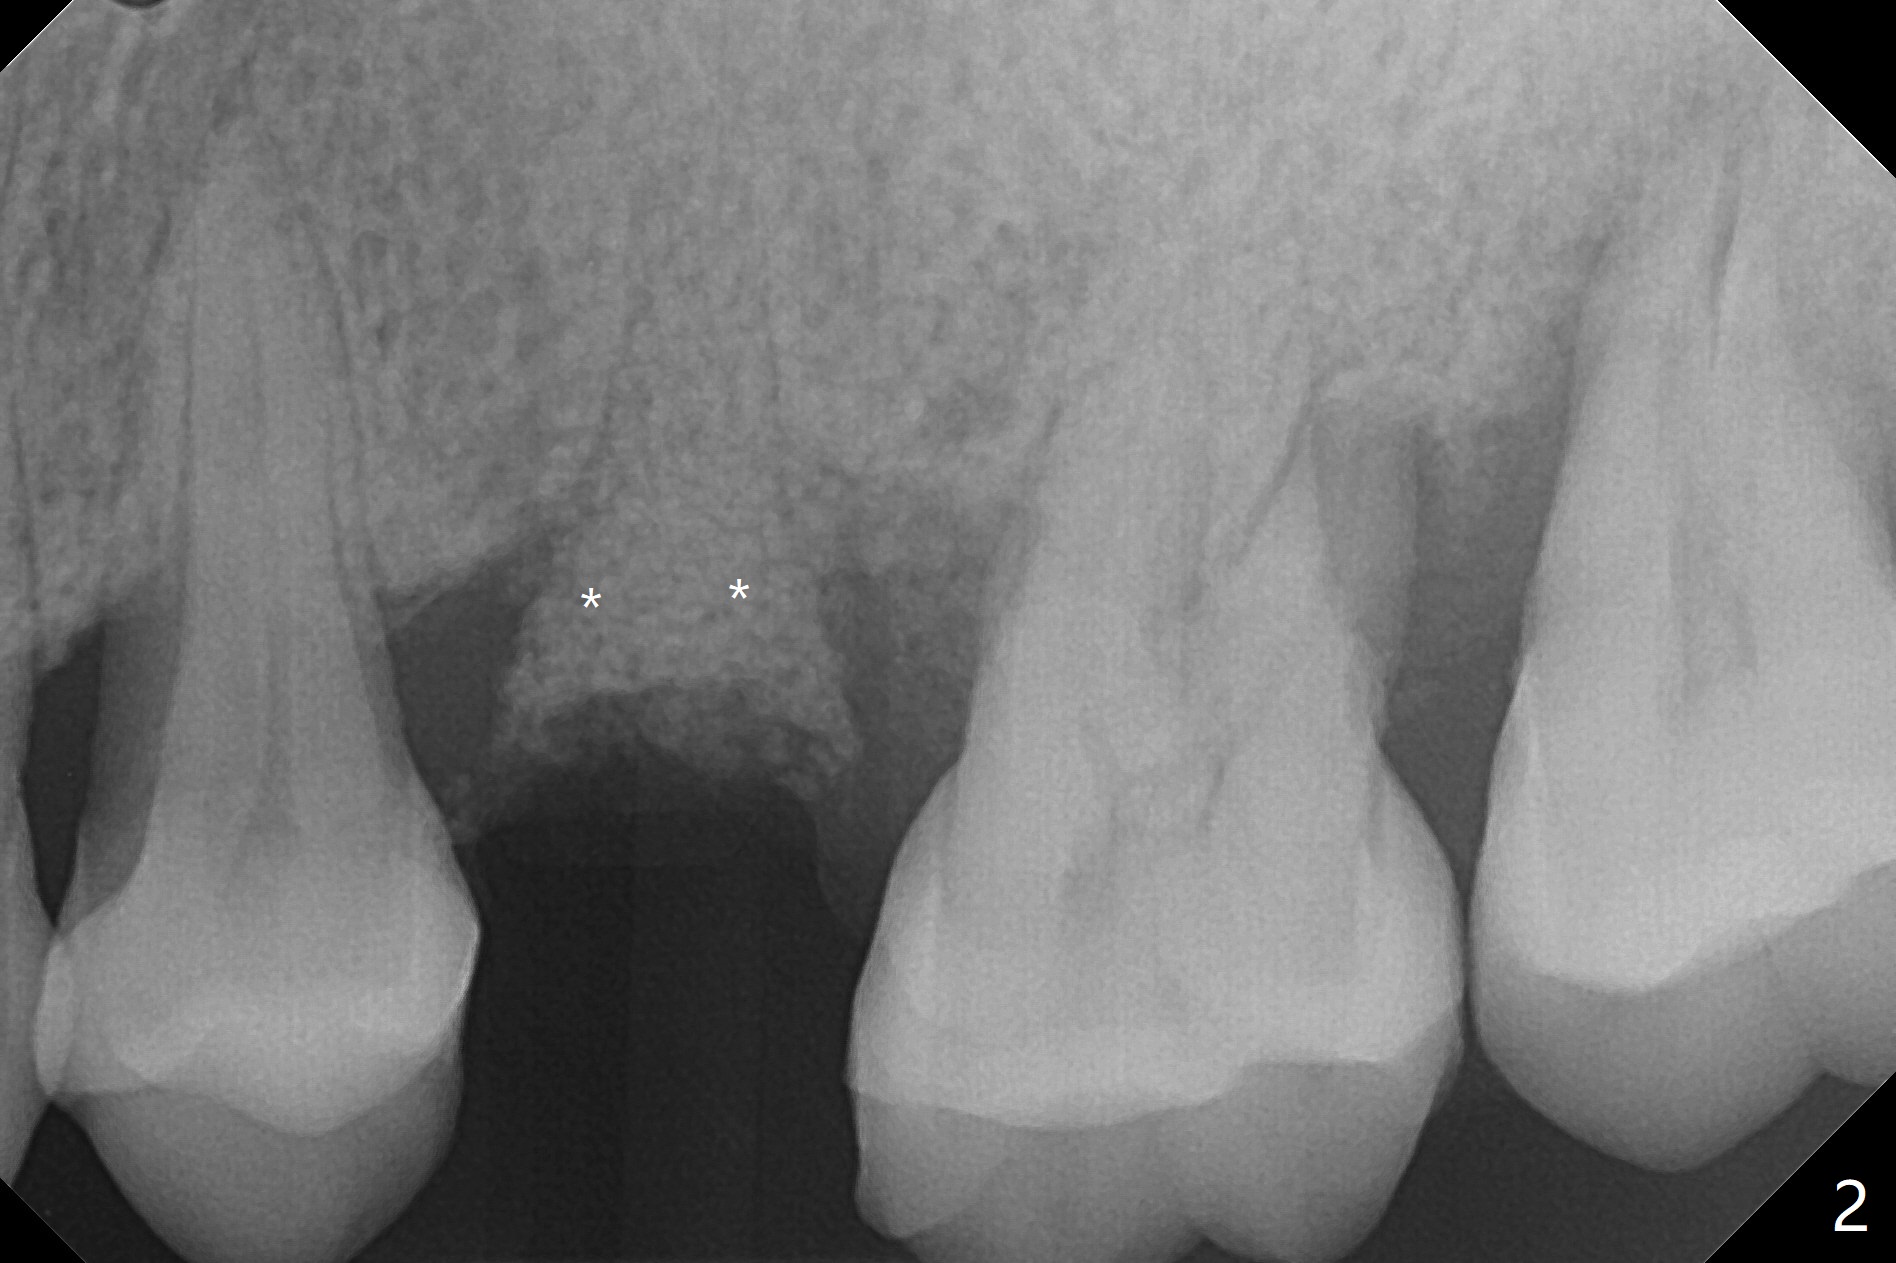

术后二周牙周敷料松动,取出后,伤口尚可(图三)。可能病人用右侧咀嚼,造成右上两个双尖牙松动疼痛,拔出后即刻种植修复,之后她能在右侧咀嚼,而食物撞击左上拔牙创疼痛,无法吃饭。术后三个月左上7疼痛,瘘道,插入牙胶尖(图四:*),根周阴影。其实腭侧根纵裂(图四,五:<),三个月已经发生(图二),可以即刻种植(图六),与5延期种植同时进行,使用导板。